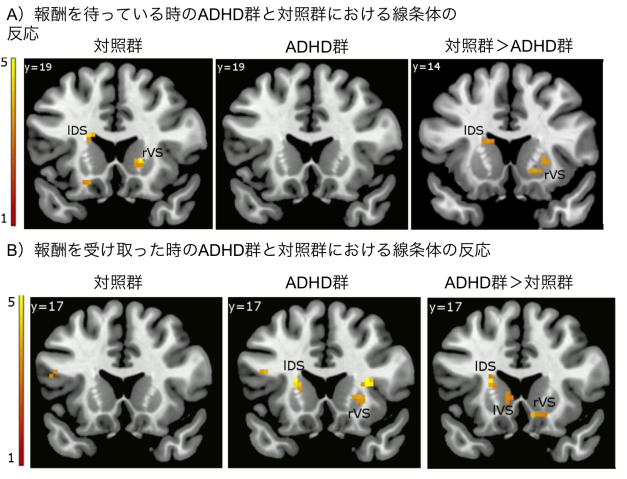

fMRI images showing differences in response to reward anticipation and delivery between adults with ADHD (ADHD group) and typically developing adults (control group). The color indicates the amount of activity, measured by changes in blood oxygen level, in the different areas of the brain.